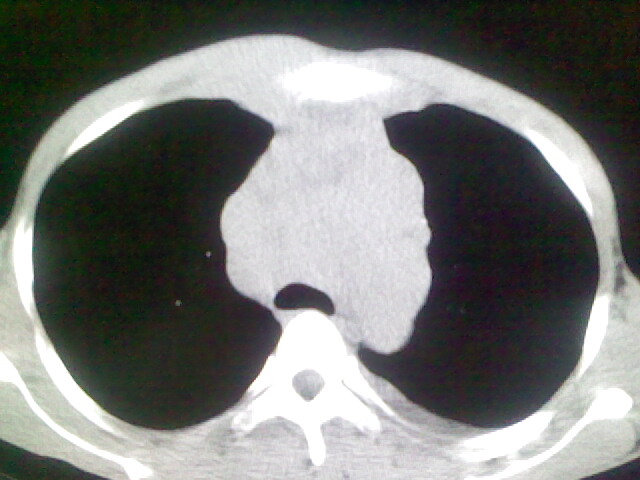

以下是引用杀毒软件在2008-9-3 6:11:00的发言:[br]侵袭性胸腺瘤------一般不侵到气管旁[br][br]考虑----纵隔淋巴瘤,心包及胸膜受累

以下是引用wzr在2008-9-3 5:30:00的发言:[br]侵袭性胸腺瘤

以下是引用随光逐影在2008-9-3 7:07:00的发言:[br]1)考虑淋巴瘤可能。2)双侧胸腔积液(以左侧为甚)。3)心包积液。